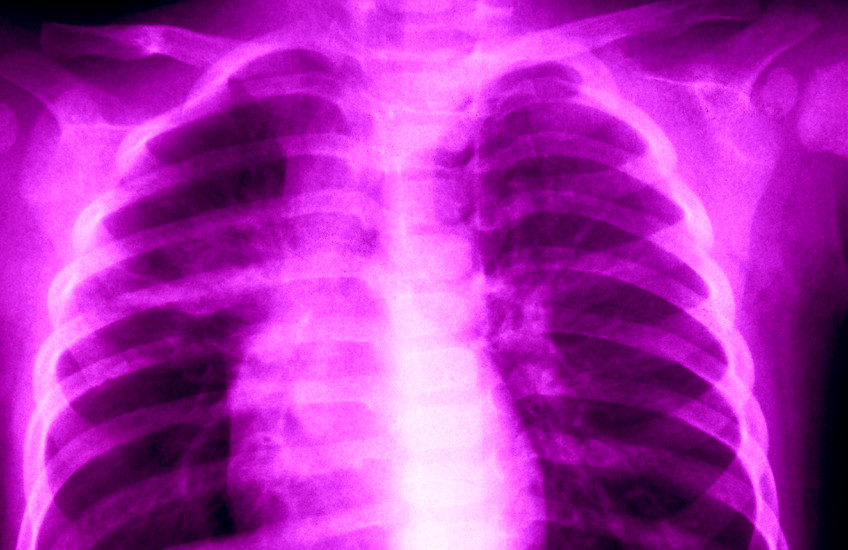

Nearly a quarter of the world’s population is estimated to be infected with Mycobacterium tuberculosis (M.tb), the pathogen that causes tuberculosis, but less than 15 percent of infected individuals develop the disease.